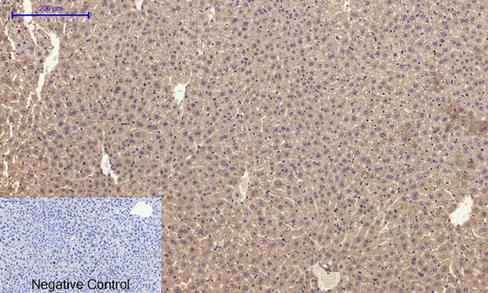

Glut4 Rabbit Polyclonal Antibody

Cat: APRab11504